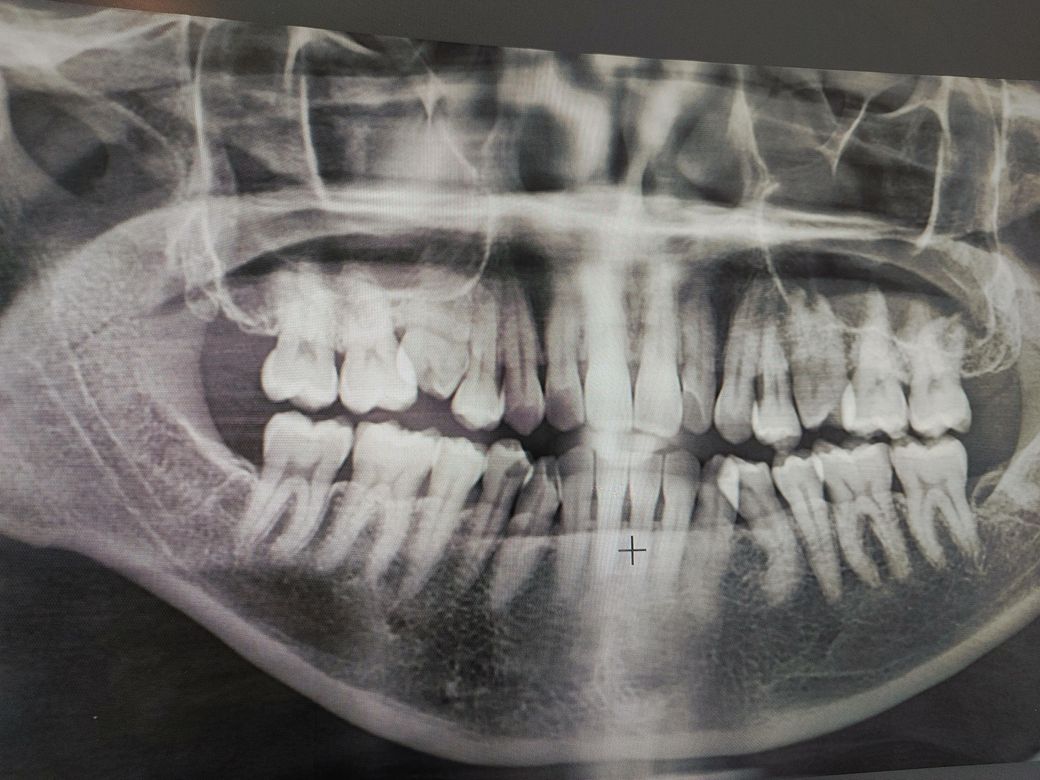

• 1번 째 사진

2. 현재로선 엑스레이 상에선 특별히 이상은 없어보입니다.

3. 첫번째 큰 어금니, 두번째 작은 어금니 사이에 음식물이 잘 끼어 충치가 잘 유발될 수 있는 구조이므로 치실질 잘해주셔야 합니다.